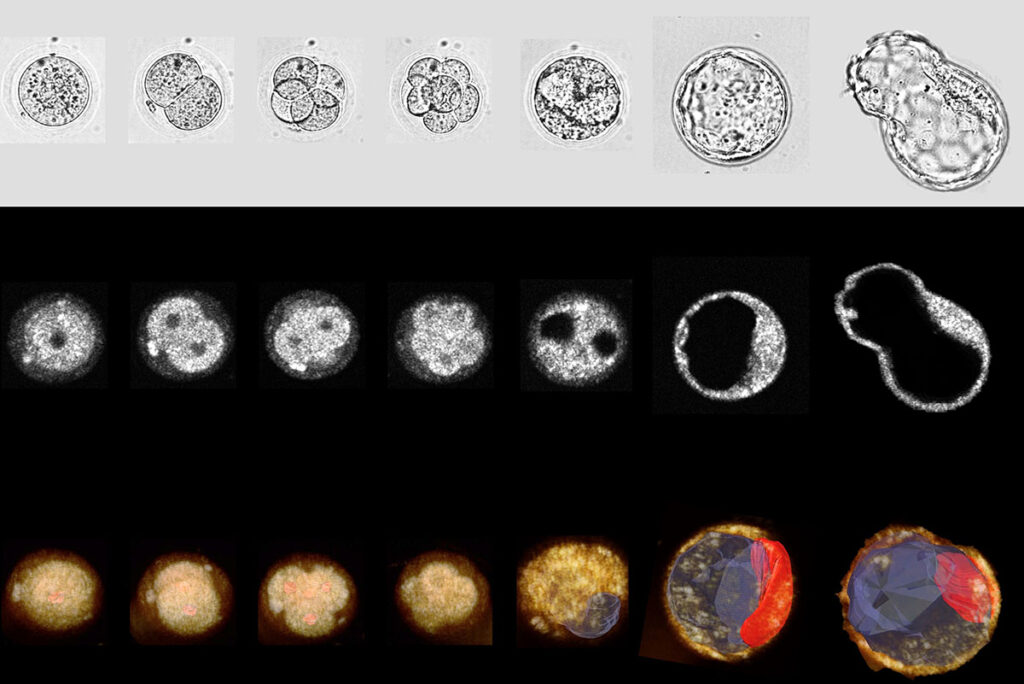

In vitro fertilization has served as the primary approach to tackle infertility for nearly fifty years, yet its live birth success rate remains below 40%. Choosing an embryo with the greatest potential might enhance the success rate, but current methods for capturing time-lapse images of developing embryos have been restricted.

A group of scientists from the McKelvey School of Engineering at Washington University in St. Louis employed dual-modality, 3D, time-lapse optical coherence microscopy (OCM) and brightfield (BF) imaging to observe mouse embryo growth and foresee successful blastocyst formation. Findings from this study, published in Communications Biology this spring, position OCM as a valid technique for selecting high-quality embryos for transfer and increasing the success rates of in vitro fertilization.